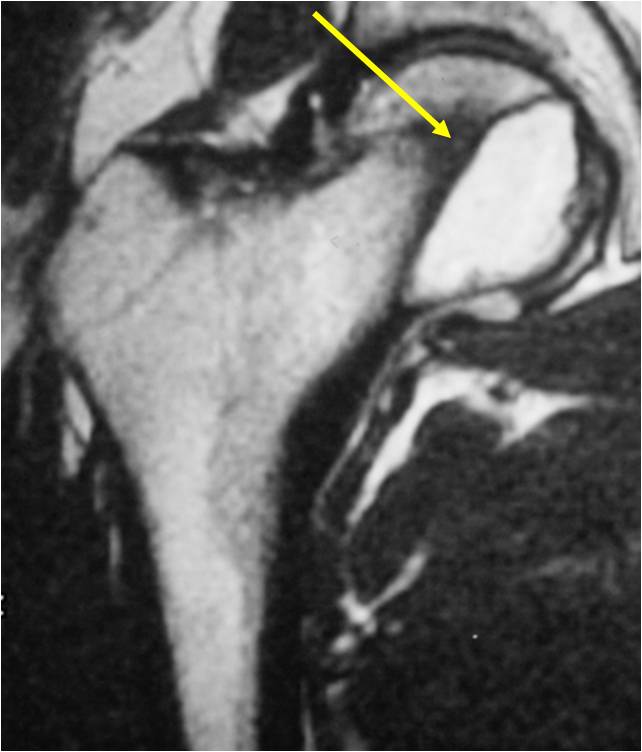

- Epiphyses of long bones

- Most commonly proximal femur, proximal humerus, distal femur, proximal tibia

- Usually osteolytic, expansile lesion

- May be focally calcified

- Often a sharp interface between tumor and surrounding bone

- Overlying cortex is usually thin, but intact